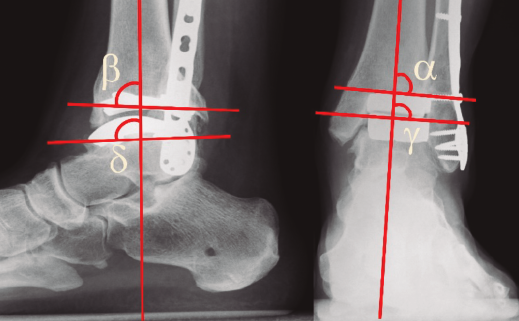

Figura 5. Control del posicionamiento de los componentes de la prótesis. Ángulos α (tibial coronal), γ (coronal talar), β (sagital tibial) y δ (sagital talar). Explicación en el texto.

En los controles radiográficos debemos valorar la correcta posición de los componentes protésicos(44) mediante la medición de los ángulos α (tibial coronal), γ (coronal talar), β (sagital tibial) y δ (sagital talar) (Figura 5). Los valores ideales de los ángulos α, γ, y δ son de 90° y de β de 84°, y se aceptan desviaciones de hasta 5°.